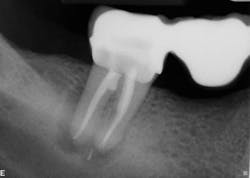

Healing is noted on the six-month follow-up (figure 4).